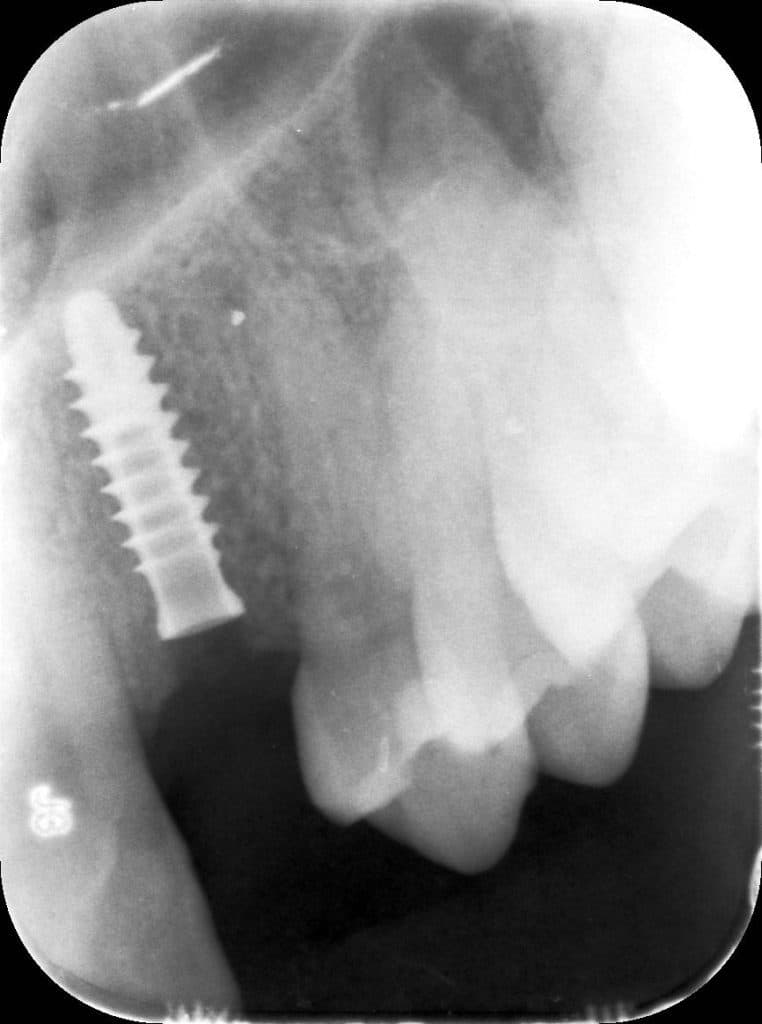

La pz N.G. di anni 52 (ASA 1) viene visitata nel mese di settembre 2017 per la mobilità ed inestetismo dell’elemento protesico 22, (foto iniziali sequenza 1) si evidenzia una frattura parziale della radice, si decide per l’estrazione ( foto sequenza 2) e sostituzione dell’elemento con un restauro implanto-protesico. Purtroppo la scarsa quota ossea apicale all’alveolo post-estrattivo (foto 2 rx) e l’alta valenza estetica dell’elemento ci rende cauti e si programma una socket preservation post estrattiva con l’ausilio delle membrane di prf (foto prf e socket sequenza 3 e 4). Durente i 5 mesi di guarigione la pz porta una protesi parziale mobile (foto 5,2) , a guarigione del sito post estrattivo si evidenzia una buona conservazione dei volumi osseo-gengivali,(foto guarigione sequenza 6) se pur presente una recessione distale all’elemnto 21.Nel mese di febbraio 2018 si procede all’inserimento di un impianto max-stability 3,75x12mm disegnando un lembo anticipato palatino per consentire un aumento dei tessuti vestibolari suturando con tecnica rool flap e trasformando l’elemento parziale mobile in una corona singola a carico immediato sul moncone temporameo applicando i concetti protesici bopt , (foto impianto moncone protesi provvisoria sequenza foto 7-8-9). Durante il periodo di maturazione dei tessuti molli vengono apportate opportune modifiche ai profili del provvisorio al fine di dare maggior spazio al tessuto gengivale, ( fotosequenza 10).Dopo circa 2 mesi dal protesizzazione provvisoria si è proceduto alla realizzazione del manufatto protesico con tecnica chair side sirona con l’ausilio del t-base (foto sequenza 11-12-13), realizzando in una sola seduta una corona in disilicato, ottenendo un risultato più che soddisfacente (Foto 14). Nel controllo a 3 mesi dal carico definitivo si apprezza la perfetta conservazione dei livelli ossei e gengivali. (foto sequenza 15).concludo con un follow up a 18 . Tengo a sottolineare che un caso come questo è stato conducibile con buoni risultati solo grazie alla piena fiducia della pz e alla sua massima motivazione e collaborazione. Ad oggi la pz sorride soddisfatta del risultato. E questo rappresenta la massima ricompensa di chi dedica tutto se stesso alla professione.